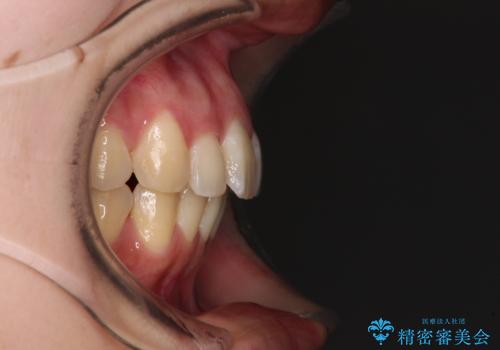

左右ともに奥歯の咬み合わせが上顎前突となっており、上顎前歯が飛び出している状態でした。

奥歯の咬み合わせ改善が必要であるため、マウスピース矯正より確実に達成のできるワイヤー矯正にて治療を行うこととしました。

奥歯の咬み合わせはしっかりと改善され、前歯の突出感も改善されました。